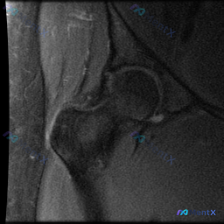

这份髋关节MRI影像下,盂唇病变可能性有多大?

看到一份髋关节MRI T1序列冠状位的病例材料,用户预设想了解盂唇病变的可能性。

- 扫描范围:单侧髋关节区域,包括股骨头、股骨颈、大转子、髋臼及其关节间隙

- T1序列特征:正常骨髓高信号,皮质骨低信号,肌肉中等信号,关节软骨及韧带清晰

- 股骨头/股骨颈:轮廓光滑,未见水肿、缺血或塌陷

- 髋臼:形态正常,未见增生或囊变

- 关节间隙:宽度均匀,未见狭窄

- 软组织:臀肌群及大转子周围未见明显异常

当前影像未见盂唇撕裂、囊肿或明确信号异常的直接征象。但盂唇病变在常规MRI序列上可能不敏感,特别是早期或微小病变。